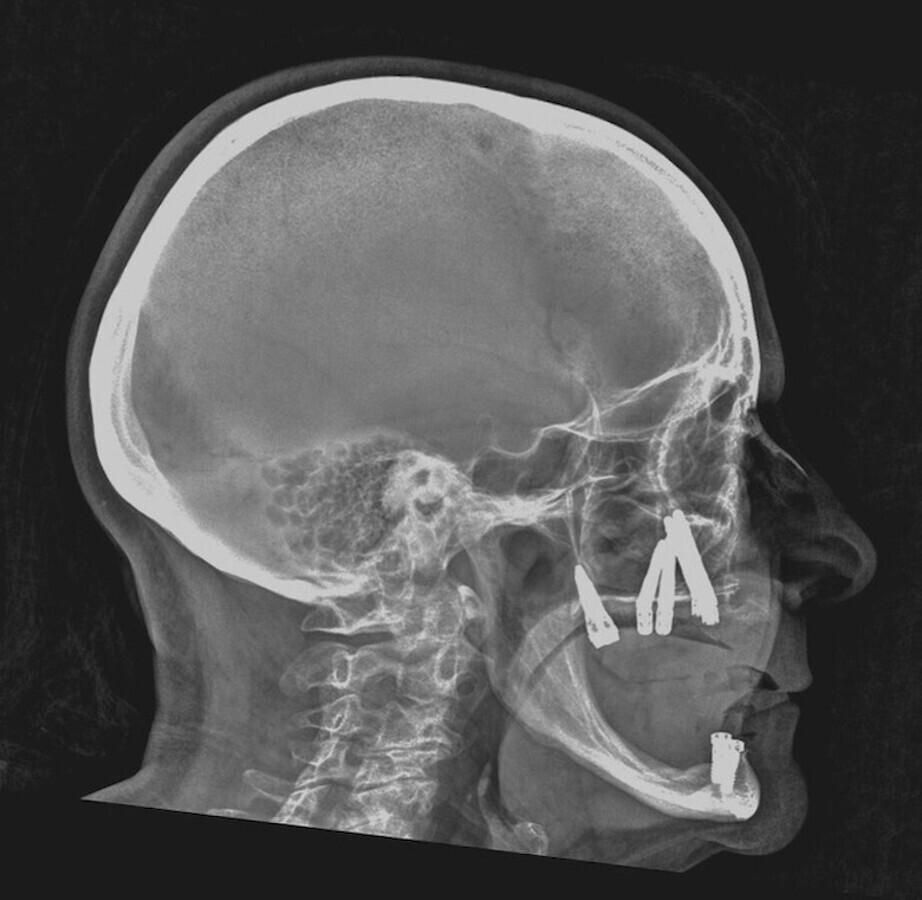

Restauración con implantes finalizada.

La implantología impulsó una mejora en la calidad de vida de los pacientes, mejorando notablemente no solo su confort y estética sino también su autoestima. Aunque pareciera poco y no lo es, evitó dañar más piezas dentarias para lograr un mismo resultado. Si todo ello es cierto, válido y genuino, el anclaje extramaxilar vino más aún, hace ya tiempo, a dar otro gran salto en la resolución quirúrgico protésica en un sesgo de pacientes que seguían excluidos de los beneficios de la implantología por razones obvias: carecían de stock óseo donde implantar.

La implantología volvió a los pacientes más ambiciosos y demandantes de importantes rehabilitaciones, y con justa razón. Hoy en día, prácticamente no hay límites ni etarios ni resortivos-resectivos en los cuales no pueda lograrse la mayor de las rehabilitaciones, el mayor gold estándar, al que los pacientes pueden aspirar: me refiero, ni más ni menos, que a reconstituir su arco dentario completo fijo. Incluso con la posibilidad de remoción y mantenimiento que un simple mortal no implantado no tiene.